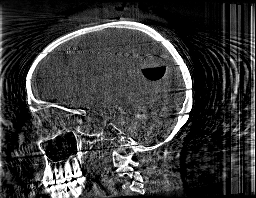

Krylov subspace methods are a powerful family of iterative solvers for linear systems of equations, which are commonly used for inverse problems due to their intrinsic regularization properties. Moreover, these methods are naturally suited to solve large-scale problems, as they only require matrix-vector products with the system matrix (and its adjoint) to compute approximate solutions, and they display a very fast convergence. Even if this class of methods has been widely researched and studied in the numerical linear algebra community, its use in applied medical physics and applied engineering is still very limited. e.g. in realistic large-scale Computed Tomography (CT) problems, and more specifically in Cone Beam CT (CBCT). This work attempts to breach this gap by providing a general framework for the most relevant Krylov subspace methods applied to 3D CT problems, including the most well-known Krylov solvers for non-square systems (CGLS, LSQR, LSMR), possibly in combination with Tikhonov regularization, and methods that incorporate total variation (TV) regularization. This is provided within an open source framework: the Tomographic Iterative GPU-based Reconstruction (TIGRE) toolbox, with the idea of promoting accessibility and reproducibility of the results for the algorithms presented. Finally, numerical results in synthetic and real-world 3D CT applications (medical CBCT and {\mu}-CT datasets) are provided to showcase and compare the different Krylov subspace methods presented in the paper, as well as their suitability for different kinds of problems.